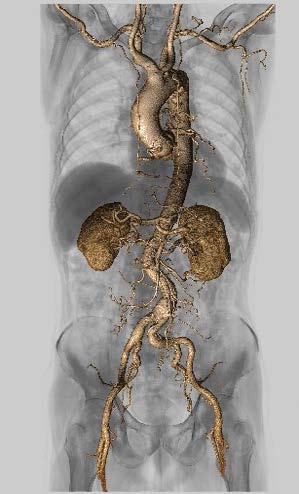

高い認識精度で3D画像作成を支援する

Abierto Vision(図3)

Aquilion ONE / INSIGHT Edition+Abierto Vision

による臨床画像

図3 大動脈解離 図3 大動脈解離

高速ヘリカルスキャンと

Abierto Visionで全身血管を描出

今回、Aquilion ONE / INSIGHT Editionの導入に合わせてAbierto Visionが稼働した。Abierto Visionは、AI技術によるさまざまな部位のセグメンテーションで高度な画像解析を可能にした医用画像解析WSとして、2024年11月に発売された。Abierto Visionでは、「Auto Extract」によってワンクリックで、頭頸部、体幹部、下肢の骨の分離抽出、脳動静脈の分離抽出を可能にするほか、冠動脈芯線をトラッキングする「Coronary Tracking」など、3D解析のワークフローを簡略化する技術を搭載している。そのほか、同社のWS「Vitrea」に搭載されていたベイズ推定法を用いた「CTボリュームパフュージョン解析(CTP解析)」などのソフトウエアも利用できる。

同院では、従来、急性期脳梗塞症例では、VitreaでCTP解析を、IVRが必要な場合には他社WSでアクセスルート解析のための血管描出を行ってきた。稲垣係長は、「Abierto Visionでは、複数のソフトウエアを同時に動かすことができるので、CTP解析からIVRのプランニングまで1台で対応できます。これらの処理が1つのWSで完結できれば、業務の簡略化やスループットの向上につながる可能性があります」と期待する。

3D画像作成は、Abierto Visionのほか他社製WSも使用して、CTAや整形外科領域などを中心に1日約30件を作成している。3D画像の作成は技師全員が行えるようにしているが、稲垣係長は、「日替わりで担当は決まっていますが、撮影補助なども兼務しながらなので、3D画像作成に専念することができません。それだけに、Abierto Visionで自動抽出の精度が向上し、件数の多い大動脈や下肢、頭部のCTAで血管が精度良く短時間で処理されれば、3D画像処理の時間短縮にもつながるのではと期待しています」と述べる。田中部長はAbierto Visionの導入効果について、「自動化によって3D画像作成の時間が短縮して、働き方改革につながるといいですね」と言う。